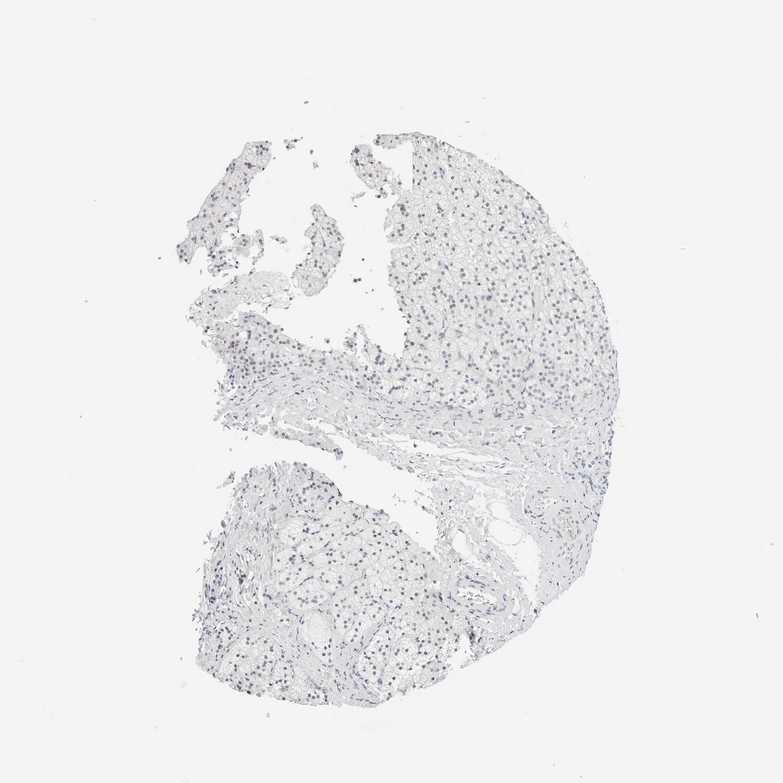

ADRENAL GLAND - Antibody stainingi

Antibody staining in the annotated cell types in the current human tissue is reported as not detected, low, medium, or high, based on conventional immunohistochemistry profiling in selected tissues. This score is based on the combination of the staining intensity and fraction of stained cells.

Each image is clickable and will lead to virtual microscopy that enables deeper exploration of all samples and also displays staining intensity scores, fraction scores and subcellular localization as well as patient and tissue information for each sample.

Antibody HPA024353Antibody HPA066523Antibody CAB002418

Glandular cells LowLowNot detected